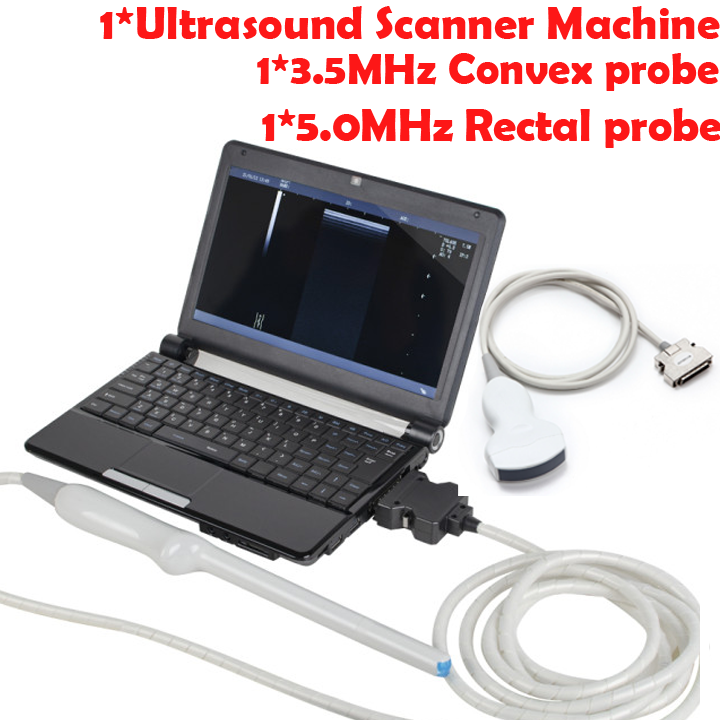

Medical Laptop Machine Ultrasound Scanner with 2 Probes

Medical Laptop Machine Ultrasound Scanner 7.5MHz Linear Transvaginal 2 Probes

The Medical Laptop Machine Ultrasound Scanner is revolutionizing the field of medical diagnostics with its advanced features and unparalleled convenience. Featuring a 7.5MHz linear transvaginal probe, it provides high-resolution images for detailed analysis. This portable ultrasound scanner delivers precise results, making it indispensable for healthcare professionals. Because it incorporates cutting-edge technology and offers unmatched reliability, this machine is perfect for clinics, hospitals, and mobile medical units.